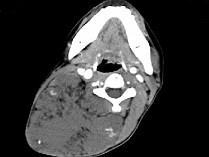

问题 女,32岁,颈部包块8年余,包块逐渐长大,CT如图所示,最可能的诊断为 ( )

选项 A、颈部神经鞘瘤 B、颈部异位甲状腺 C、颈部横纹肌肉瘤 D、颈部巨大血管瘤 E、颈部神经纤维瘤

答案 D